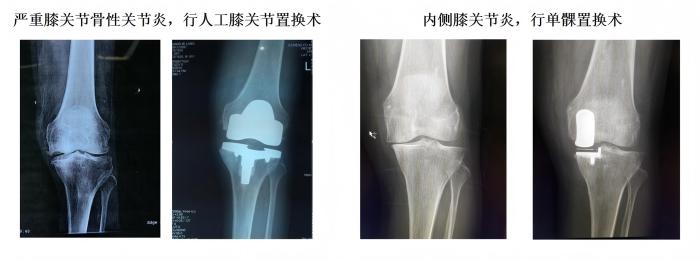

1、常规完成复杂全髋、膝关节置换手术(水泥型、生物型)、单髁置换手术、胫骨高位截骨手术、复杂保髋手术、股骨头坏死综合治疗、高龄老人髋部骨折综合治疗。

学科简介:91club 骨科是集医疗、教学、科研的重点科室,2018年评为中国创伤救治中心建设单位,2019年评为福建省骨科联盟成员单位、厦门市医学优势亚专科。科主任个人获得厦门市政府拔尖人才,厦门市劳模等荣誉。目前设有关节运动医疗组、骨折创伤医疗组、脊柱医疗组、小儿骨科医疗组,常规开展髋关节、膝关节置换,单髁置换,反肩置换,髋膝关节翻修术,胫骨高位截骨矫形,椎间孔镜髓核摘除、脊柱UBE镜下融合,肩关节镜肩袖修复、膝关节镜前后交叉韧带重建,复杂骨盆骨折、胫骨平台骨折复位固定。于国内外期刊发表专业学术论文累及50余篇,SCI 8篇。